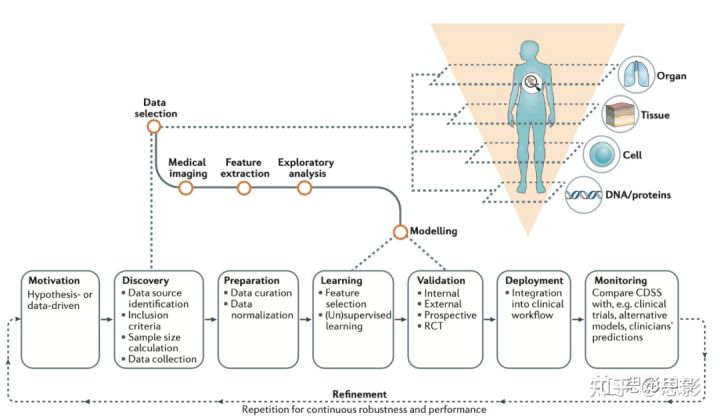

影像组学方法被定义为定量映射,即提取与预测目标相关的许多医学图像特征如临床和基因组特征并建模分析。影像组学研究可分为五个阶段:数据选择、医学成像、特征提取、探索性分析和建模(图1)。为了评估影像组学研究的质量,我们提出了影像组学质量评分(RQS)。

图1:描述影像组学实现流程图和RQS应用的流程图。

该流程包括影像组学分析中的必要步骤。RQS对研究方法和分析进行评分,从而鼓励最佳科学实践。RSQ,影像质量评分;VOI,感兴趣区。

图7,RLHC的方法学过程概述,以及影像组学工作流程如何适应CDSS的开发。

数据选择、发现、收集和准备、模型开发\验证和实施、临床效用评估以及通过持续重复过程最终完善(整个过程中都需要质量控制和保证协议)。